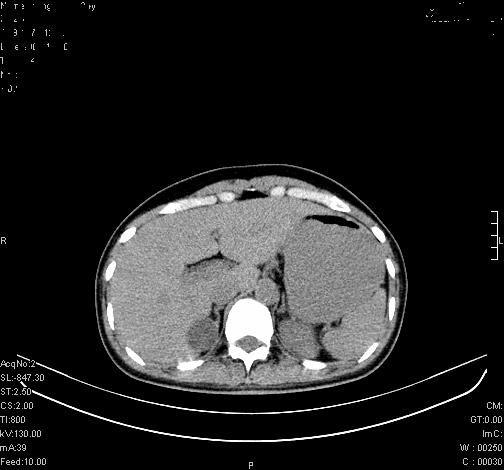

标题: CL0340:【】肾上腺囊肿,比较典型。

患者为年轻女性,查体发现右侧肾上腺囊性占位。无临床体征。

这么漂亮的图像,一看一目了然。典型的右侧肾上腺囊肿,周围有钙化。感谢搂主!

“肾上腺囊肿组织学分为4类:1)内皮细胞性,2)假性囊肿,3)寄生虫性,4)上皮细胞性。其中内皮细胞性最为常见。假性囊肿多为肾上腺内出血后遗留囊腔,囊壁无上皮细胞。寄生虫性多为包虫病引起。上皮性则很少见。”

这么明显的弧形钙化,多考虑包虫病所致的寄生虫性囊肿。

右侧肾上腺囊性密度灶囊壁有钙化。考虑肾上腺囊肿,结核?

右侧肾上腺囊肿,周围有钙化。